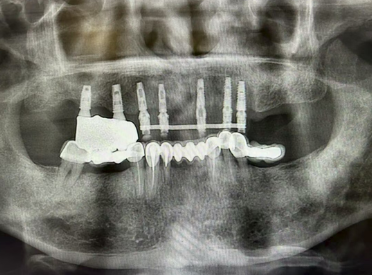

由于右侧种植体是数年前的老款,现在已经没有对应的复合基台,左侧又存在多颗烤瓷冠,丁爷爷的口腔情况较为复杂。为此,口腔科特邀请南京市第一医院医联体专家薛昌敖主任和宋鑫主任成立了专项诊疗小组,通过口腔CT仔细评估牙槽骨情况,反复研讨后制定了个性化修复方案:保留右侧原有种植体,调整匹配基台;左侧拆除烤瓷冠,拔除松动牙后即刻植入新的种植体,两侧同期制作临时义齿,实现“即拔、即种、即用” 的三重保障。

手术当天,凭借术前的充分准备,在两位主任的默契配合下,从拔除患牙到植入种植体,再到安装临时义齿,整个过程仅用两个多小时,创伤小、出血少,丁爷爷全程无明显不适。“手术一点都不痛,医生和护士都特别细心,就像家人一样照顾我。” 术后丁爷爷握着医护人员的手连连道谢并合影留念。